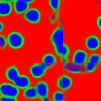

The task of nuclei segmentation can be roughly divided into two stages: the first stage is extracting the foreground(nuclei), the second stage is segmenting the connected foreground area into separated nuclei and finding out the boundary of each nucleus. Our method intends to merge these two steps by extracting the nuclei and their edges at the same time. That is the reason why it is named ”nuclei-boundary(NB) model”. As shown in Fig.3, the output of the NB model has three channels, each has the same height and width with the input image. Its values represent the probabilities of each pixel being , or class, respectively. The manual annotation for our segmentation problem is the boundary of each nucleus. A pixel belonging to the class means that it is on or inside an annotated boundary and within 2 pixel from the boundary. Pixels of the class are those that are inside annotated boundary but are not pixels. Correspondingly, the output can be regarded as an RGB image and the estimated maps of the , and are represented by red, green and blue, respectively, as shown in Fig.3. To generate the ternary mask for training, we apply a morphology operator to each nucleus to obtain the pixels, and then subtract pixels from the nucleus to get pixels.

Figure 6 shows how our method segments the nuclei step by step. The color variety is well controlled by the color normalization procedure. The prediction result shows clear nuclear areas and nucleus boundaries. In the final segmentation result and ground truth image, each nucleus is represented by a different color.